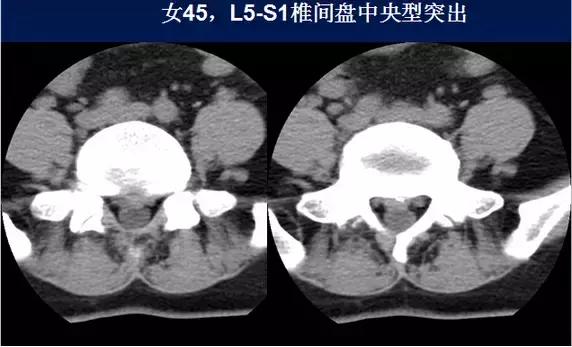

⑴中央型:椎间盘影局限性超出椎体边缘,硬膜囊可受压,硬膜外脂肪间隙变窄、消失,可伴纤维环钙化。